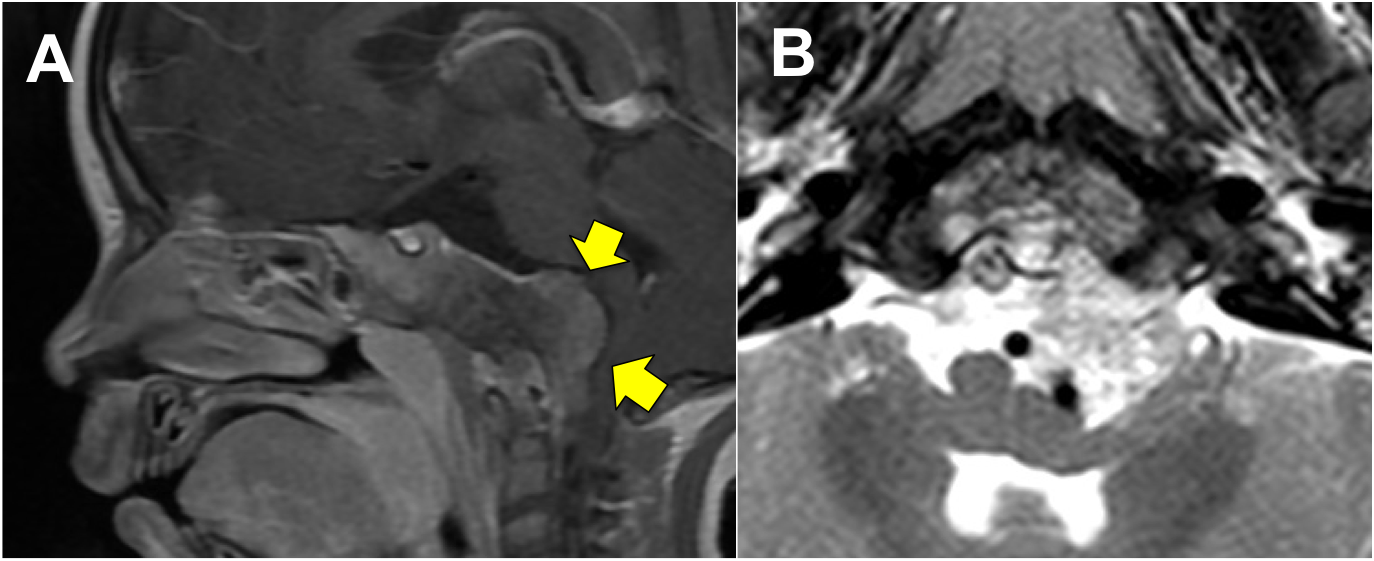

Introducción: La cirugía endoscópica endonasal se ha convertido en una herramienta fundamental para el manejo de patologías que comprometen la base de cráneo. En casos bien seleccionados, estas técnicas permiten resecciones quirúrgicas con una menor morbilidad sin comprometer los principios oncológicos de resección. Con el desarrollo de instrumental especializado, nuevas tecnologías y la experiencia de los cirujanos, la cirugía endoscópica endonasal se usa cada vez más en cirugía de base de cráneo en niños.

Diseño: Estudio observacional descriptivo de tipo serie de casos. Metodología: se describe la experiencia con pacientes pediátricos llevados a cirugía endoscópica endonasal para manejo de tumores de base de cráneo en el Instituto Nacional de Cancerología entre julio de 2014 y diciembre de 2016.

Resultados: Fueron intervenidos 8 pacientes entre los 2 y 14 años, con una edad promedio de nueve años y un seguimiento promedio de 16 meses. En el 75% se hizo una resección total del tumor. Un paciente requirió una reintervención y un paciente fue sometido a radiocirugía post-operatoria. 1 paciente falleció a pesar de múltiples intervenciones, quimioterapia y radioterapia.

Conclusión: La cirugía endoscópica endonasal para tumores de base de cráneo puede ser utilizada de forma segura en los pacientes pediátricos, es una técnica que en casos bien seleccionados pueden ofrecer excelentes resultados disminuyendo la morbilidad y complicaciones de las técnicas abiertas.